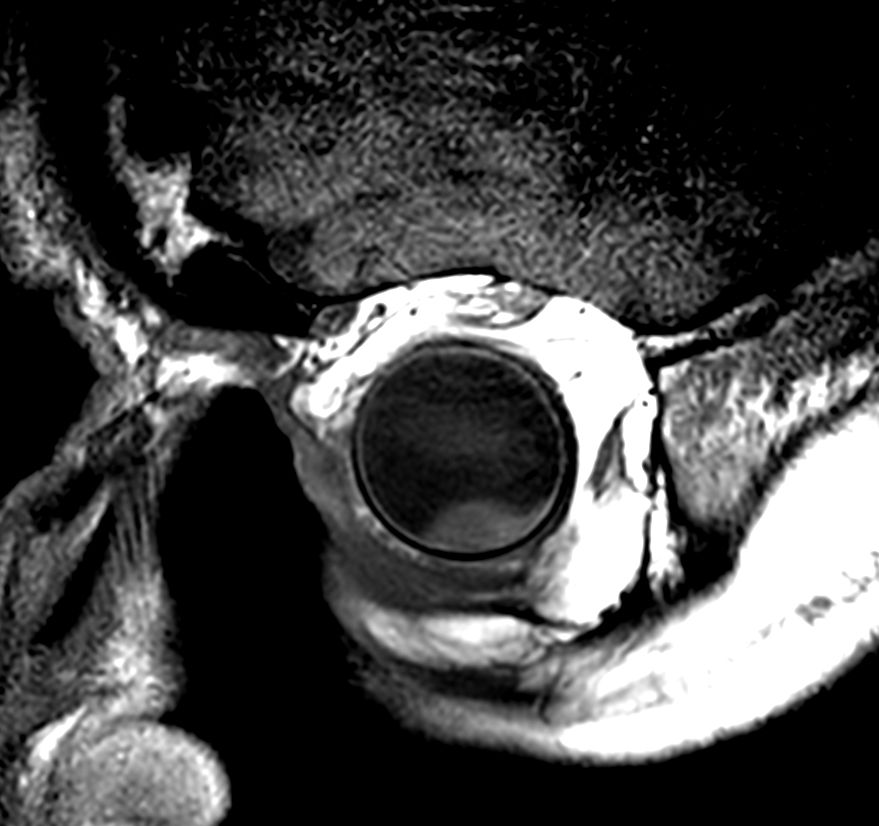

4 different 3D isotropic sequences, T1W with and without fat saturation, T2W and T1W fat saturation post-contrast are used to evaluate the tumor prior to treatment. Isotropic sequences are used to allow for good quality multiplanar reconstruction corresponding to the location of the tumor; as the tumor can be located anywhere in the eye, optimal visualization often requires an assessment of different oblique planes, which is facilitated by the 3D isotropic sequences. The pre-contrast sequences help evaluate the tumor size and location and the post-contrast sequence provides additional information such as identifying tumor that has seeped through the sclera behind the eye and differentiating tumor vs associated retinal detachment.

Higher in-plane resolution 2D sequences are used to better evaluate the tumor and screen for infiltration to the adjacent structures, which can have direct therapeutic consequences.